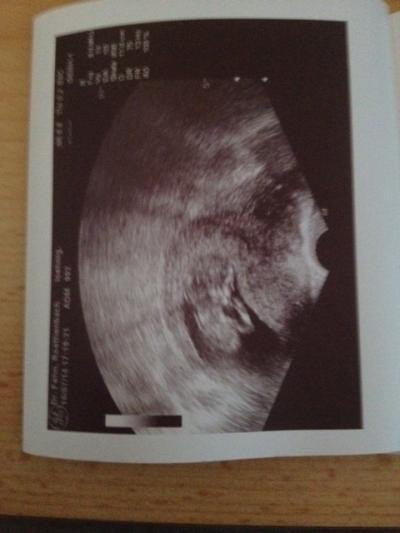

Huhu Mädels, ich war heute auch beim FA, Krümelchen geht es supi, ist 5,5 cm groß und hat so fleißig geturnt, das meine FÄ fast kein Bild machen konnte . Mei ET wurde auch korrigiert, statt der 26.01 ist es jetzt der 22.01. Es ist escht toll schwanger zu sein LG Michaela

Bild zu Zurück vom FA - Forum für Januar - Mamis